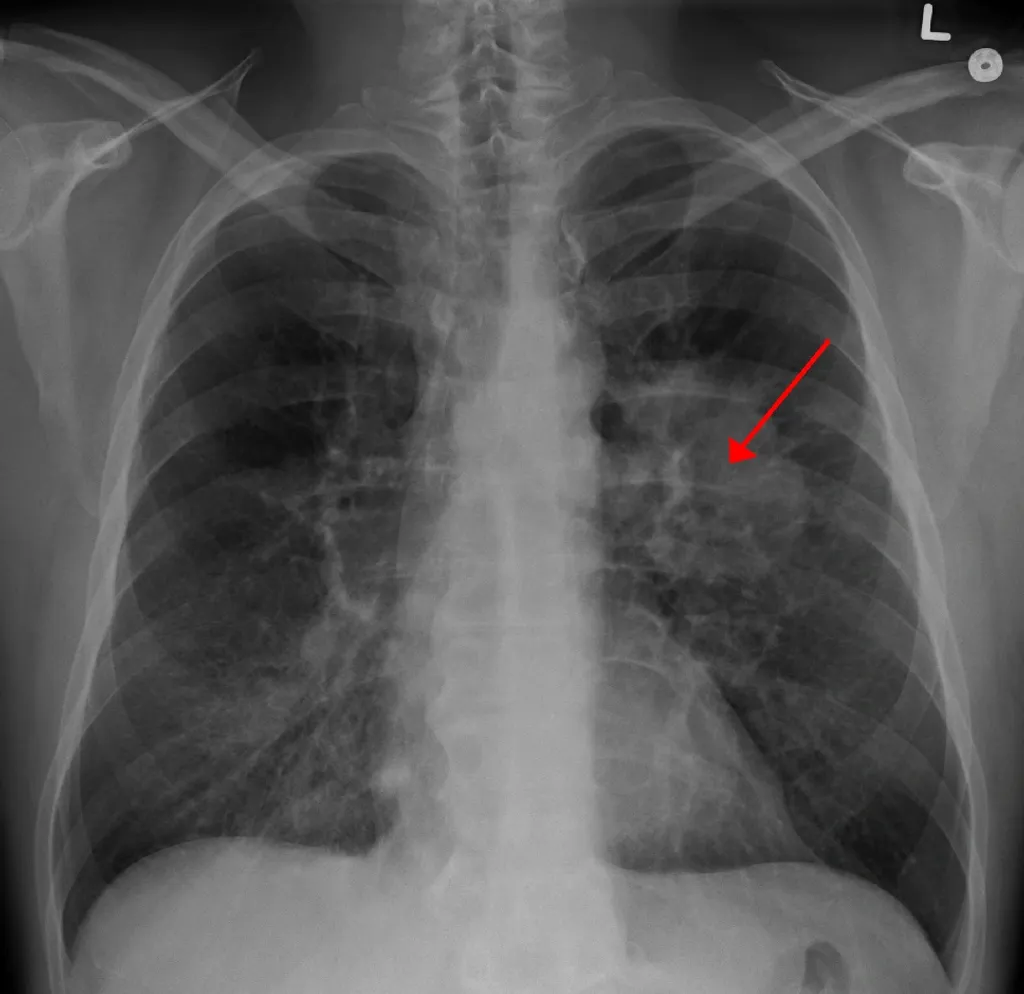

മേൽപ്പറഞ്ഞ ലക്ഷണങ്ങളിലൂടെയോ, എക്‌സ്‌റേയിൽ കാണ പ്പെട്ട സംശയാസ്പദമായ വ്യതിയാനങ്ങളുടെയോ അടിസ്ഥാനത്തിലാണ് തുടർ പരിശോധനകൾ നിർദ്ദേശിക്കുന്നത്.

• സി.ടി. ചെസ്റ്റ് - കോൺട്രാസ്റ്റ് മരുന്നു നൽകിയിട്ടുള്ള സി.ടി സ്‌കാൻ രോഗനിർണ്ണയത്തിൽ വളരെ പ്രധാനമാണ്.